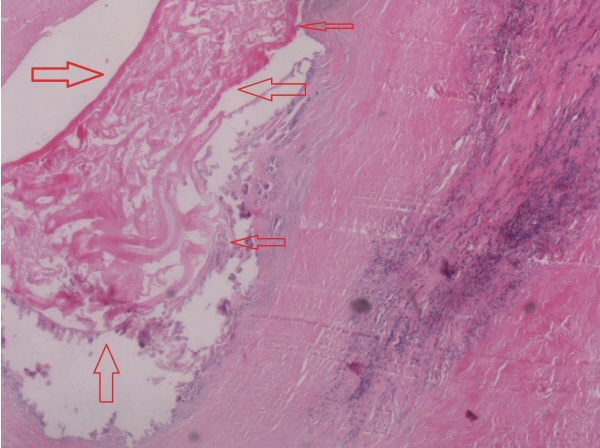

Fig. 4). Furthermore, the patient’s hydatid-enzyme immunostaining test showed weak positive.

Fig. 4The pathological examination of surgical specimen manifested that alveolar cysts (the site indicated by the arrows) could be seen in bile duct epithelial tissues (H&E,×400).